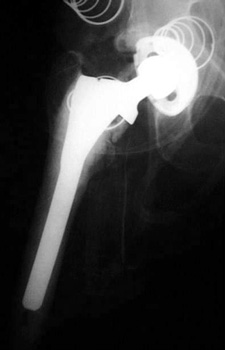

LOOSENING

No prior studies available. Abnormally widened interfaces about femoral component at Gruen zones 1, 6, and 7. Osteolysis at Gruen zone 5 with marked thinning of femoral cortex placing patient at risk for pathologic fracture.